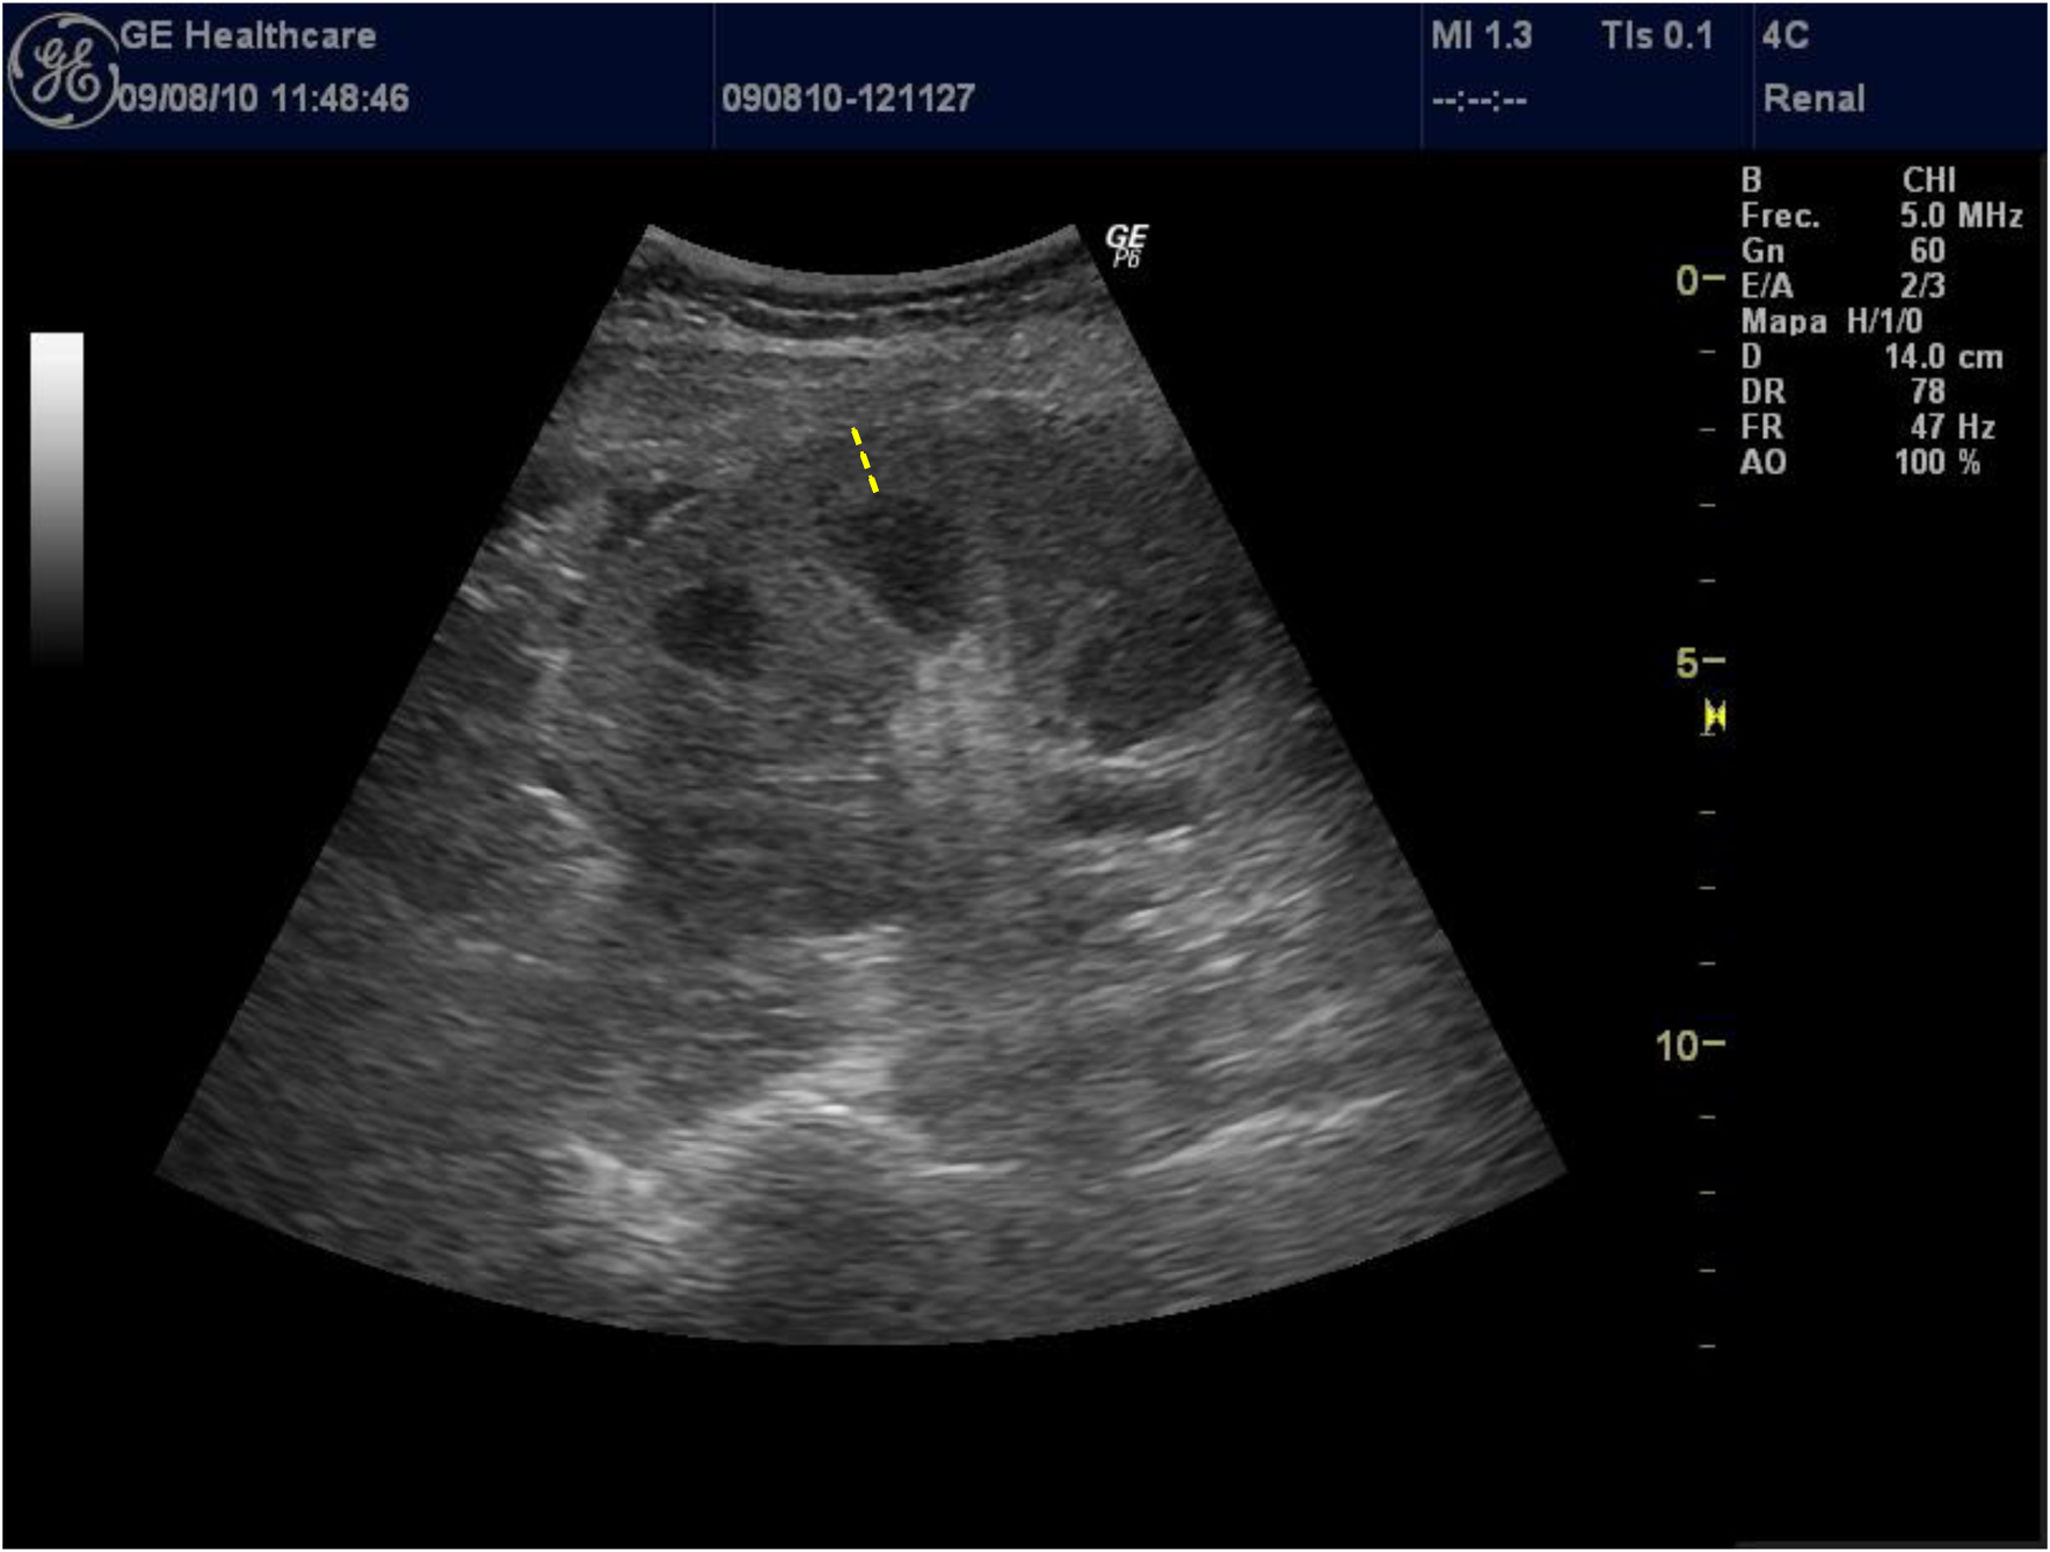

The thickness of the renal cortex is rarely used by researchers because of the difficulty of measuring it in patients with poor corticomedullary differentiation, which is relatively common in patients with advanced CKD. Given that this interface is difficult to identify, reproducibility in related measures is low, and so few studies use it; this translates to a lack of consistent data on the association between renal cortical thickness and impaired renal function. Similarly, Beland et al.13 demonstrated that the thickness of the cortex was closely correlated with the eGFR (Fig. 2).

The width of the kidney is poorly correlated with the eGFRa parameter with, even when it is corrected for height; thus, it should not be considered in the evaluation of patients with CKD.1,14